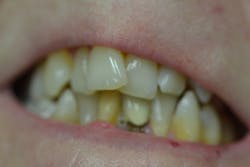

Figure 4: Maxillary anterior left

Her periodontal probing depths ranged from 2 mm to 6 mm, with as much as 4 mm of recession noted in some areas. Tooth No. 19 had a fractured off DL cusp to the gumline with decay close to the nerve; No. 29 had deep DO decay that would require endodontic treatment, buildup, and a crown to repair or possibly extraction; and No. 31 was unrestorable with buccal decay to the nerve, through the furcation, and at the bone level (figures 1–6). Faced with that treatment plan, she would also need four quads of scaling and root planing with anesthetic. We were able to coordinate the schedule to extract No. 31 directly after her periodontal treatment while she was still anesthetized.